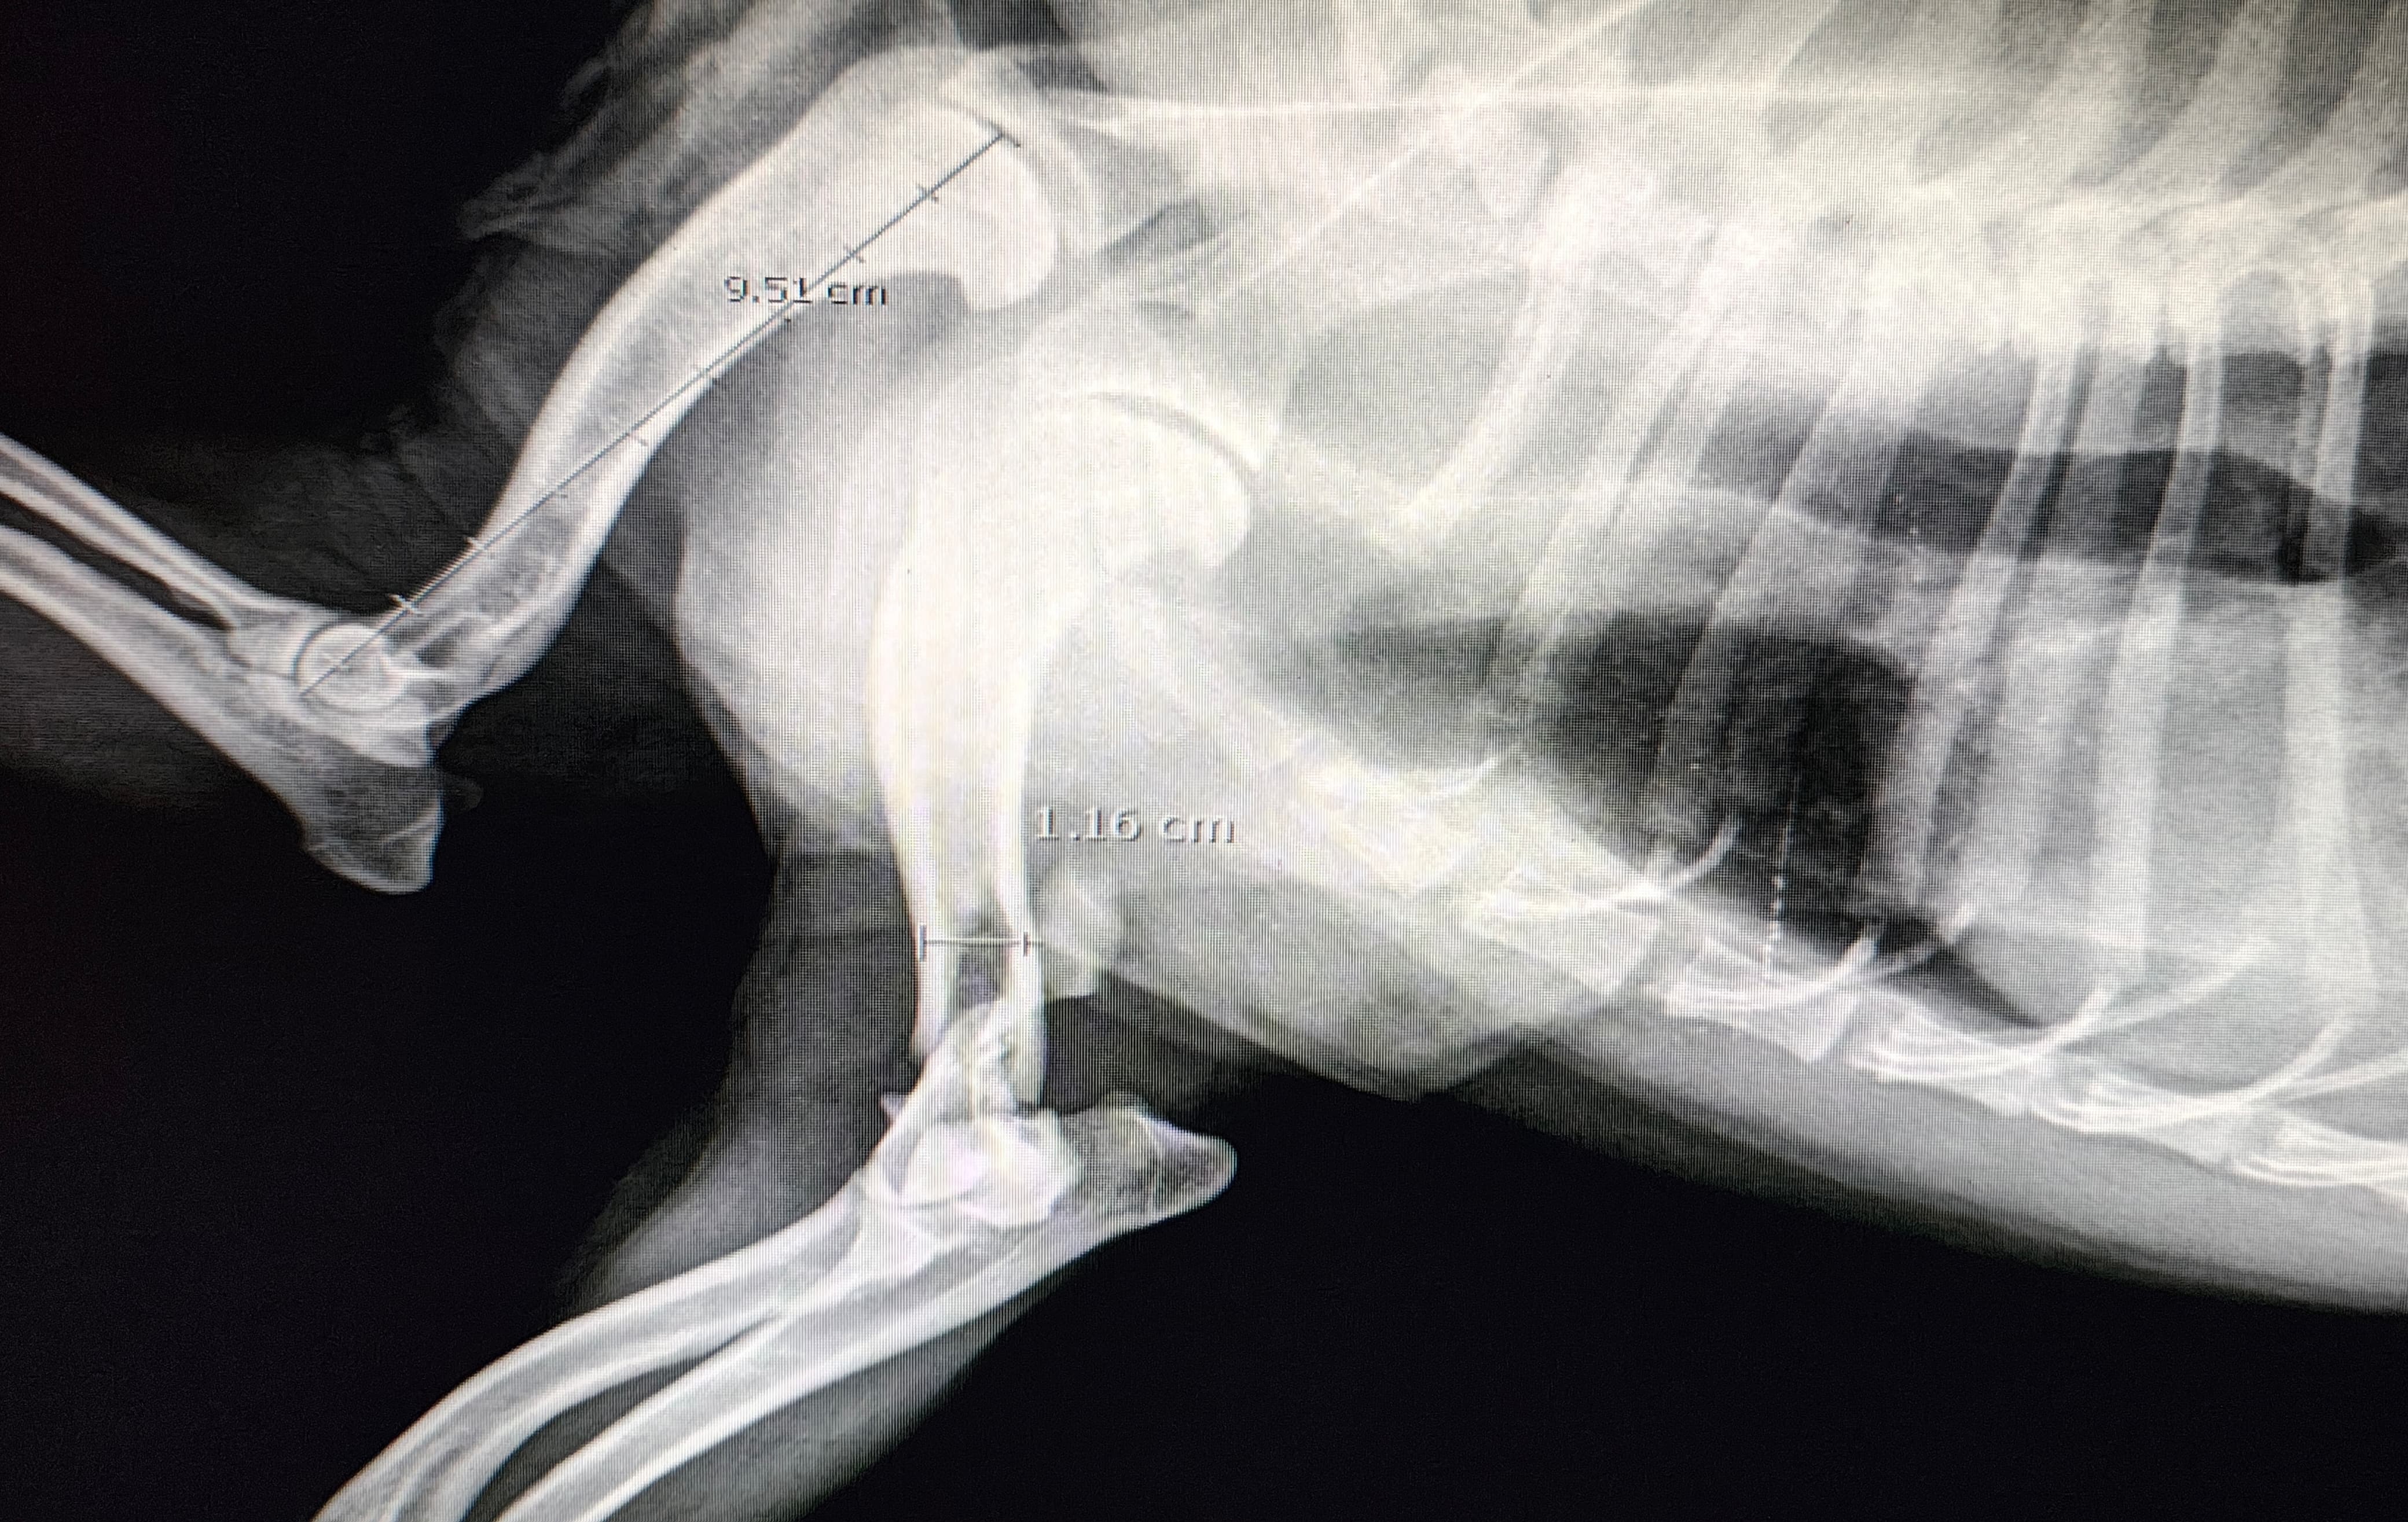

Hoy fui a ver a Friky a la Veterinaria Patas Descalzas. Despertó de la anestesia y está muy bien. En las nuevas radiografías ya se aprecio mejor y a detalle sus fracturas, que fueron en 3 partes. Entonces ya autoricé para que se le realice la cirugía indicada, que se realizará el Jueves 25 y se quedará todavía hasta el Lunes 29 para estar en observación y recuperación. El total de todo el proceso se me costeo al final a 7000 MXN, hoy pague la mitad y con sus donaciones terminaré de pagar lo que falta y para comprar medicamentos que se me indiquen para su tratamiento que falte. Nuevamente les agradezco a todos los que me apoyaron, yo sé quiénes son, así que estoy eternamente agradecido, no solamente yo, también Friky. Aún así los mantendré al tanto de lo que suceda en próximos días. Saludos!